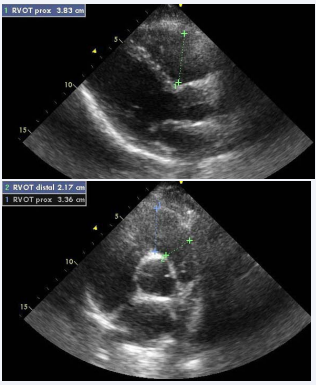

The left PSAX view demonstrating RVOT at the level of the pulmonic valve yields the ‘‘distal diameter’’, while the left PLAX view provides for the measurement of the proximal portion of the RVOT, also attributed to as ‘‘proximal diameter’’ (Figure 3).

Figure 3: Measure of RVOT (Parasternal long axis and Parasternal short axis).

Diameter > 27mm at end-diastole at the level of pulmonary valve insertion (‘‘distal diameter’’) indicates RVOT dilatation [1].